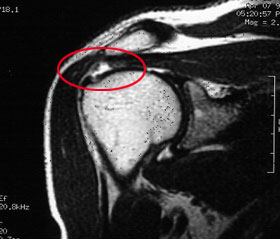

Röntgen:

Die bildgebende Diagnostik umfasst neben Röntgenaufnahmen der

Schulter in 3 Ebenen, die Aufschluss über die knöcherne

Darstellung der Schulter ergeben, die Sonographie und die Durchführung

einer Kernspintomographie der Schulter, um neben der Rupturgröße

die Qualität der Muskulatur beurteilen zu können.

Abbildung:

MRT einer Rotatorenmanschettenruptur |